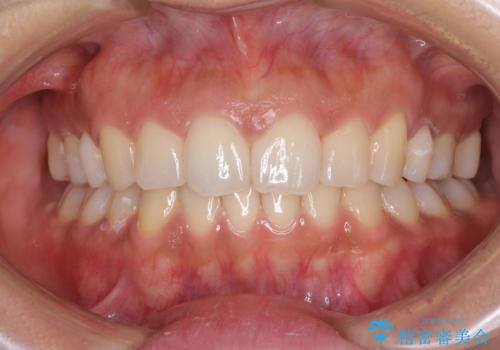

すきっ歯とオープンバイトをインビザラインで改善

- 前歯の上下スペースと前歯の隙間を気にして来院された患者様です。

インビザラインにより上下の前歯の隙間を閉じていくこととしました。

上下の隙間に舌が入り込むことが、すきっ歯やオープンバイトの原因であったため、舌の筋肉のトレーニングも並行して行い、後戻りの抑制を図りました。